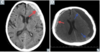

Hemorrhagic strokes are caused by either [bleeding] or [bleeding]

Hemorrhagic strokes are caused by either **subarachnoid hemorrhage** or **intracerebral hemorrhage**

39

The pathology shown may cause [type stroke]

The pathology shown may cause **ischemic stroke** * *ie atherosclerosis --> thrombotic stroke*